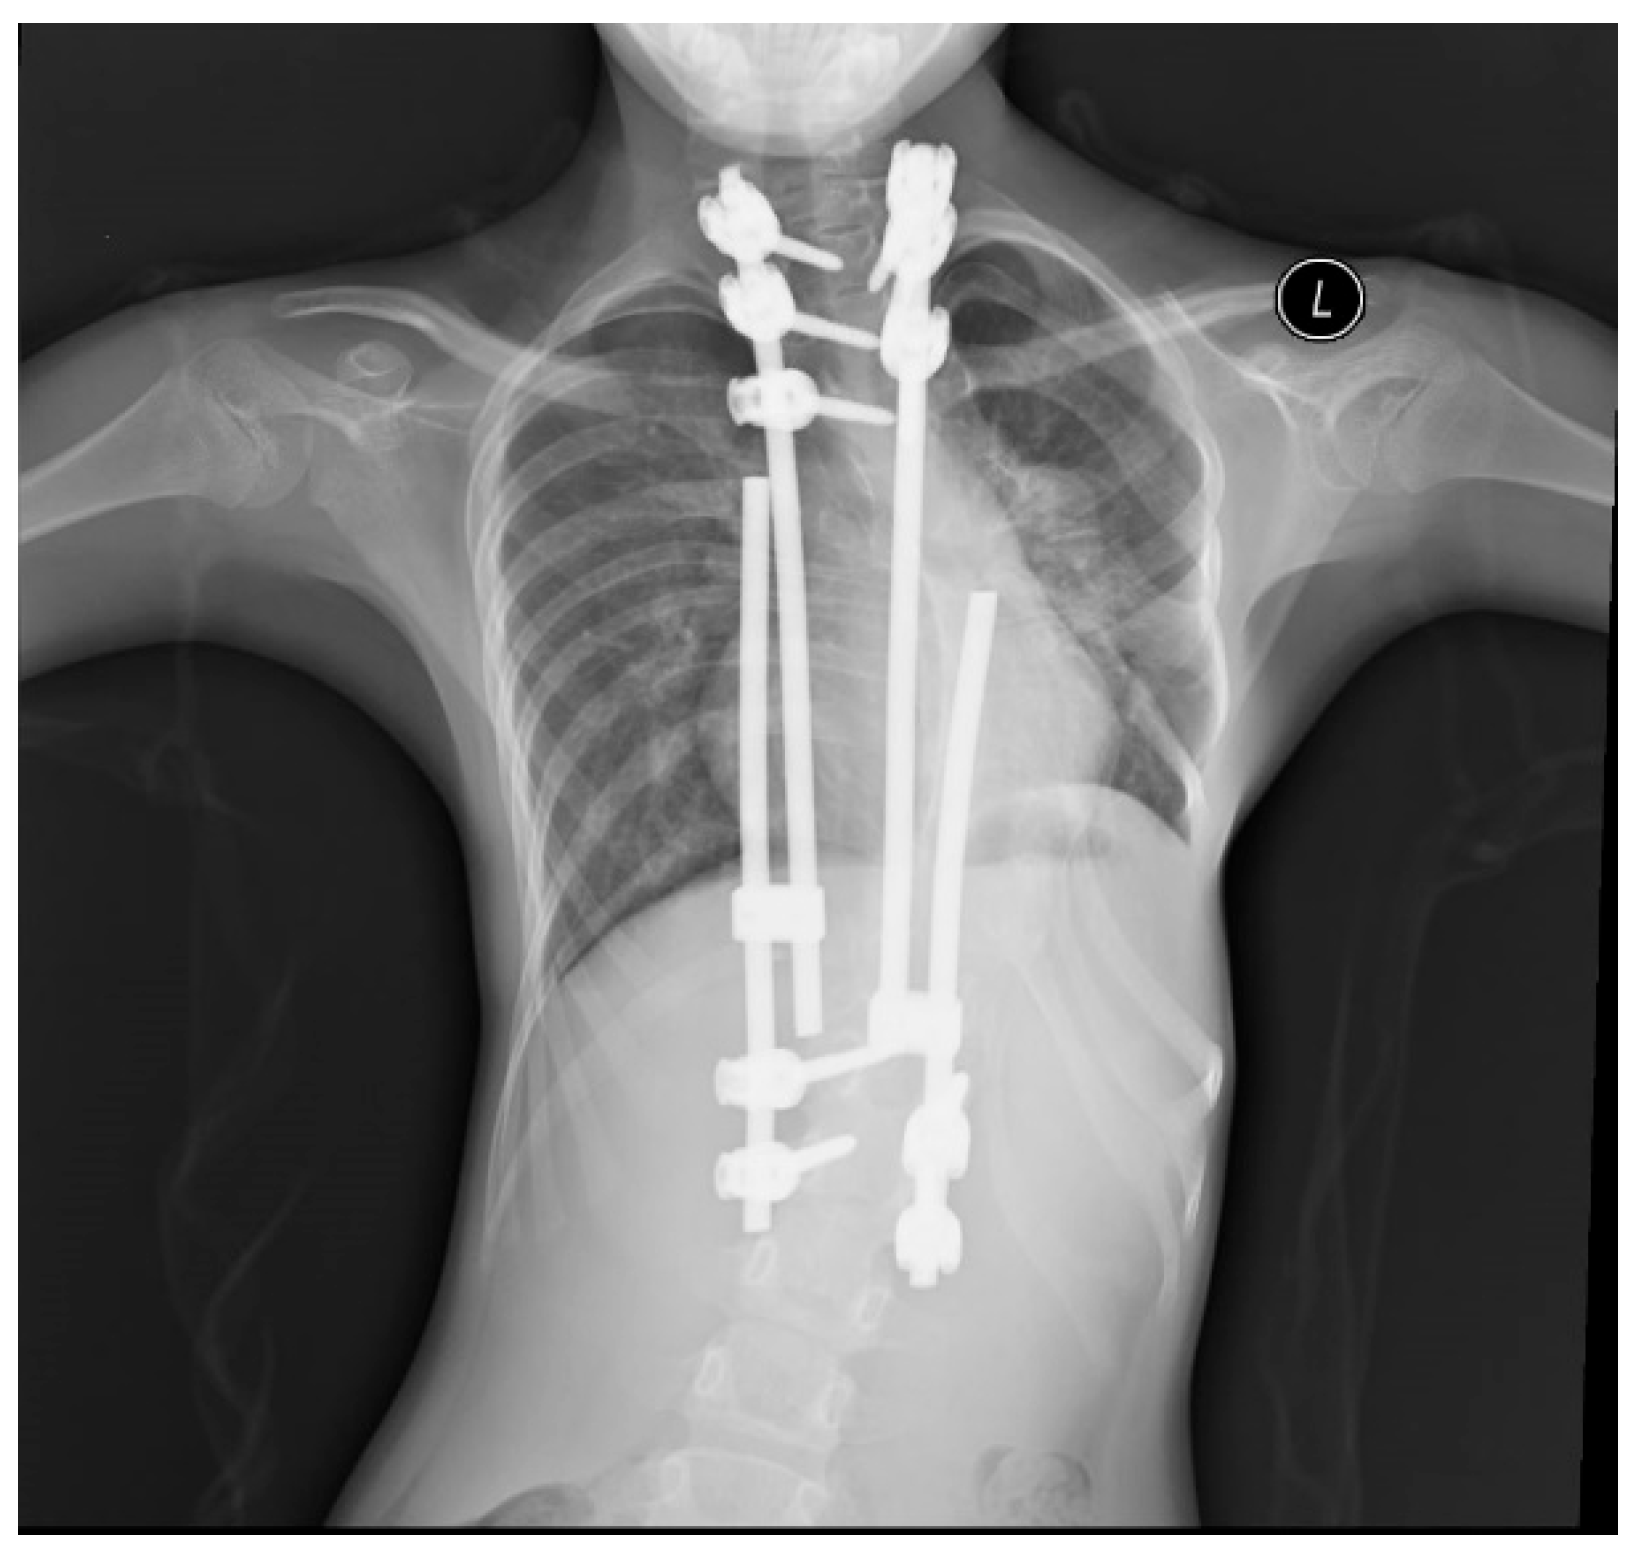

Supplementary Material FileA 7-year-old girl was taken to Women and Children’s Hospital, Qingdao University for a heart murmur. Echocardiography (Echo) showed atrial septal defect (ASD) of 13 mm (Fig. 1) with enlarged right atrium and right ventricle, slightly dilated pulmonary artery (17 mm), and left ventricular ejection fraction (LVEF) of 65%. Due to severe scoliosis, the girl underwent five spinal operations and dual growth rods at Beijing Children’s Hospital. It is indicated by our physical examination that the child had a thoracic deformity with left chest collapse.

Figure 3: Chest radiograph showed that the spine was corrected by a dual growth rod.